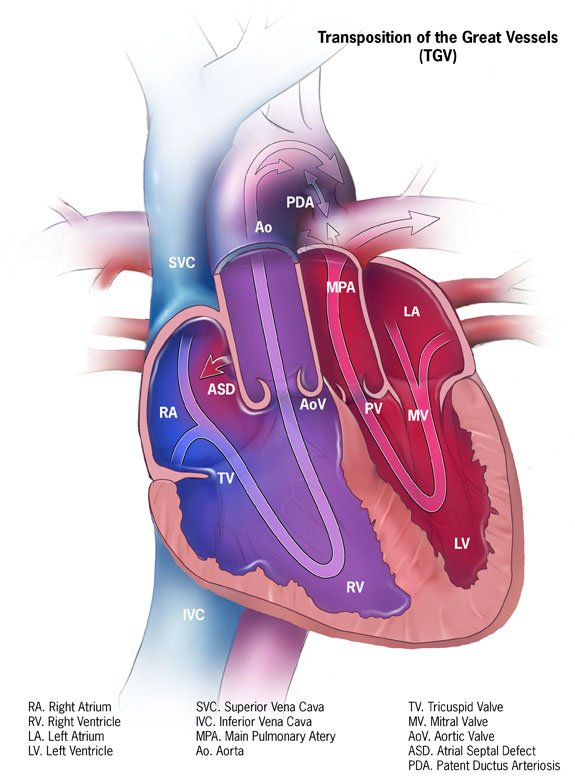

Transposition of the Great Vessels

Transposition of the great vessels is characterized by the aorta and pulmonary artery emerging from the right and left ventricles, respectively.

Gestational diabetes is a risk factor for transposition of the great vessels.

Transposition of the great vessels has an early cyanotic presentation.

Systemic and pulmonary circuits do not interact.

After birth, shunt formation (enabling blood to mix) is necessary for survival.

Prostaglandin E1 (PGE1) can be given to keep a patent ductus arteriosus (PDA) open until a permanent surgical repair is made.

Transposition of the great vessels results in left ventricular atrophy and right ventricle enlargement.